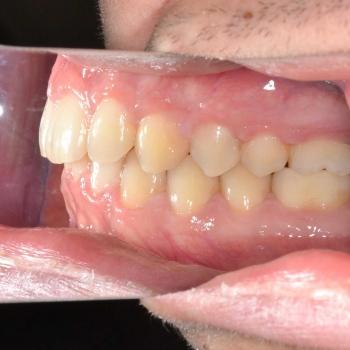

Ádám kitartásának köszönhetően a kezelés végére minden maradó fog a helyére került és egy esztétikailag és funkcionálisan is tökéletes harapást kaptunk.

A kezelés teljes időtartama: 3 év